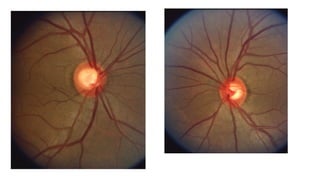

• #19 Large cup healthy rim = not glaucoma Normal mri